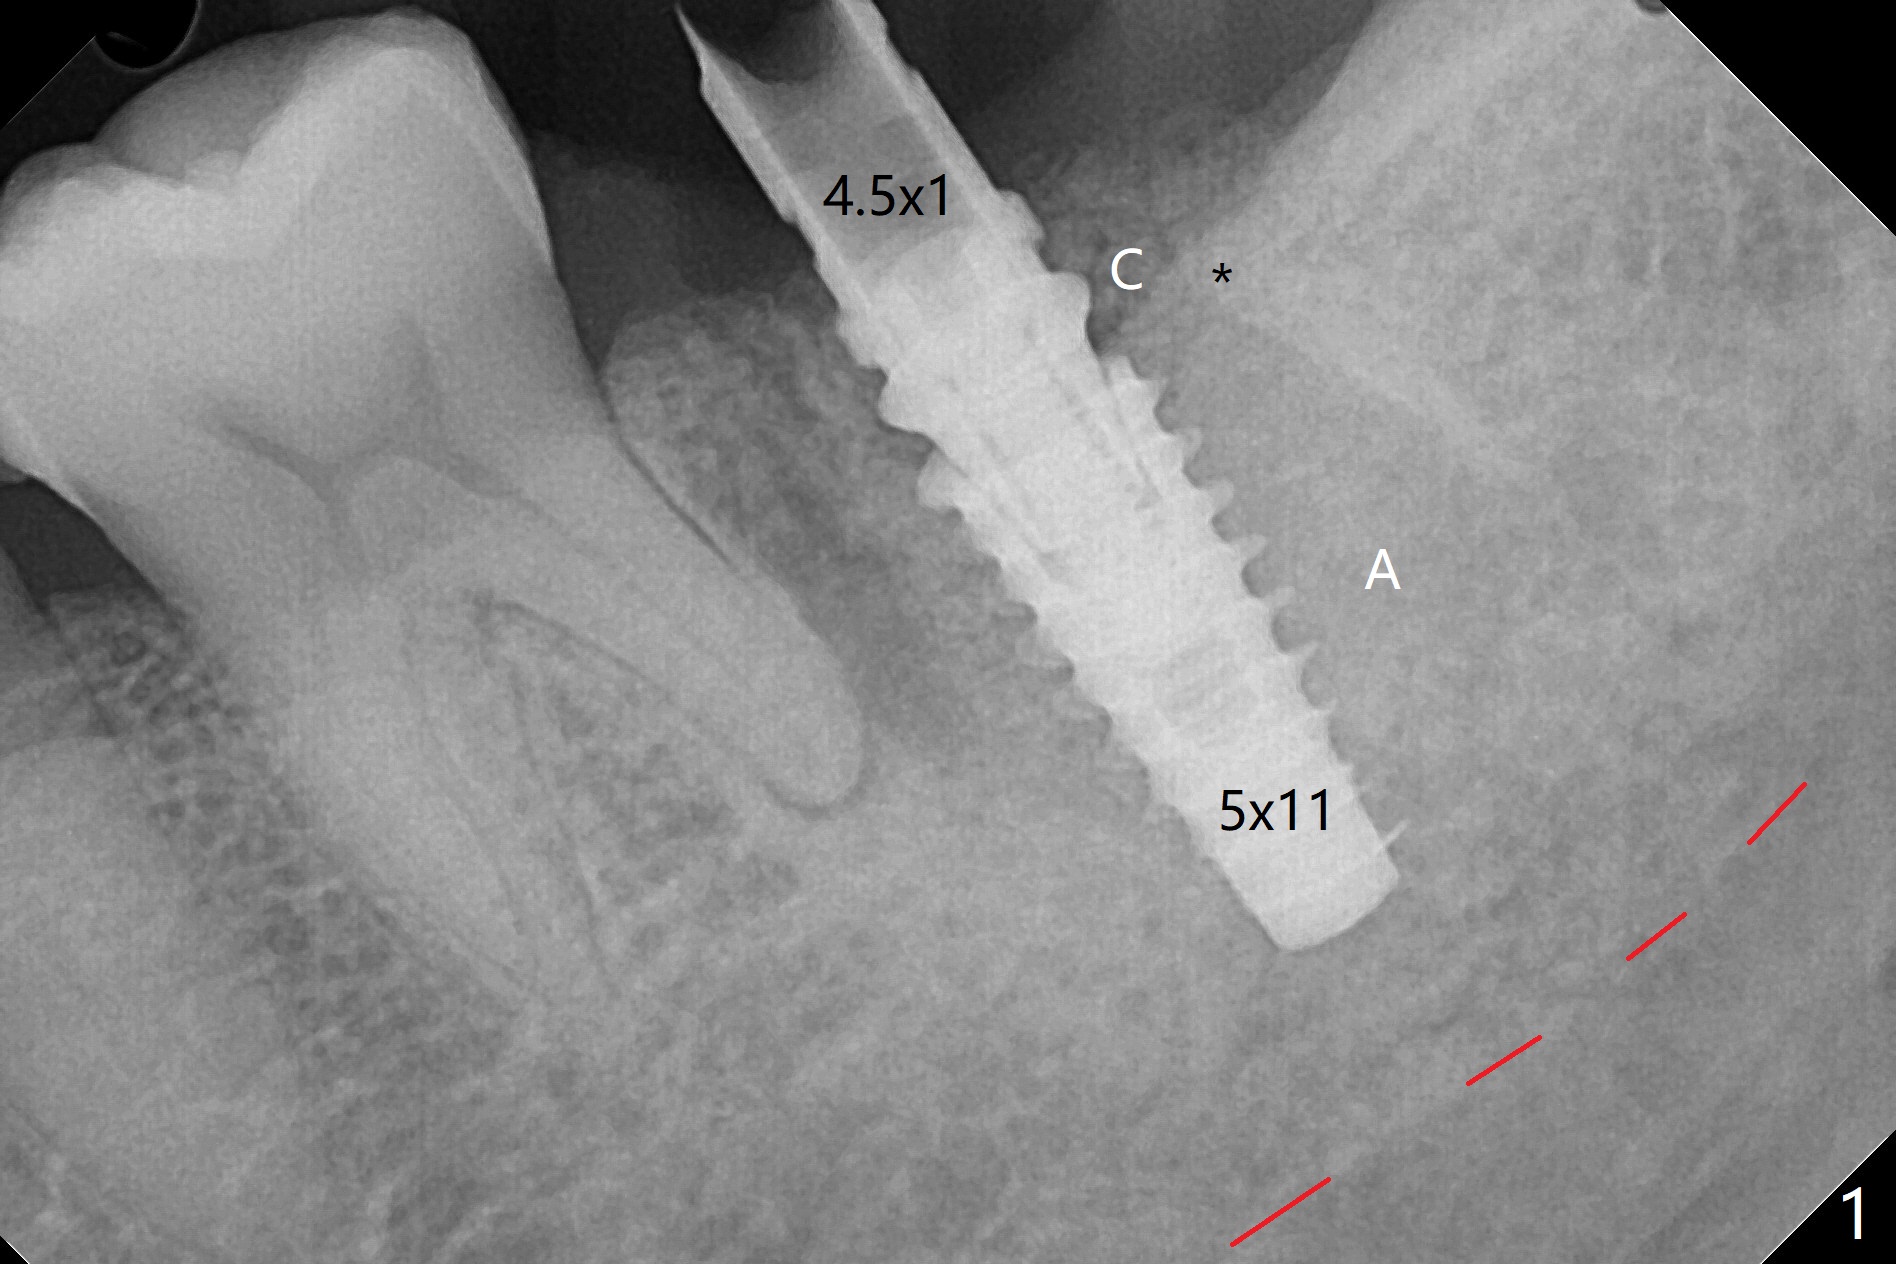

After placement of a 5x11 mm implant and cover screw at #18, allograft mixed with PRF (sticky bone) is placed in the peri-implant space, but it appears that bone density in the apical region (Fig.1 A) is lower than that in the coronal one (C) because of a constriction between the implant and the distal crest (*). Ideally the undercuts (Fig.2 *) of the extraction socket (black area) should be identified. Place bone graft in the undercuts (Fig.3 red circles) after osteotomy (white outlines) and before implant placement! A 4.5x1 mm temporary abutment is placed for an immediate provisional. The 2nd shortcoming of this case is that the implant is placed a little buccal. The papilla mesial to the immediate provisional (Fig.4 P) looks normal 4 days postop (no food impaction is expected when a final restoration is cemented). Additional acrylic (*) was placed to close a buccal gap when the provisional was seated with the temporary abutment. The patient reports loss of a piece of material in 4 days. It must be the additional acrylic, since it is absent 6 weeks postop (Fig.5). The provisional (Fig.5 P) looks wide, probably related to post-extraction gingiva and bone atrophy (Fig.6, 7 *). Bone graft (Fig.6 <) becomes a component of the gingival cuff. The provisional is re-trimmed for better oral hygiene. The gingival cuff is basically healthy 3.5 months postop, although the temporary abutment is loose and the implant is tender to rewinding and winding (Fig.8). The implant seems to remain non-osteointegrated 3.5 months postop (Fig.9). Although the bone density around the implant increases nearly 6 months postop (Fig.10), the implant remains tender when a 5x4(4) mm pair abutment is tightened. The healing abutment is reused. The bone density around the implant increases 11 months postop (Fig.11). Uncover is done with 5.5 mm profile drill. One month post uncover (12 months postop), the implant remains unstable (Fig.12). Prepare sticky bone x1. Make incision for exploration, including retightening the implant after Titanium brush and H2O2 Q-tip rubbing. If needed, a larger and shorter UF implant is a replacement (Fig.13). The implant is removed, cleaned with Titanium brushes and H2O2 in vitro and repositioned 12 months postop (Fig.14: arrow (gaps: post granulation tissue removal)). The gaps are regrafted with sticky bone and covered with PRF membrane and Cytoplast. Although the patient complains of severe pain the first 2-3 postop, the wound is apparently healing 12 days postop. The Cytoplast is exposed asymptomatic 5 weeks postop (Fig.16) and removed (Fig.17). The wound appears to have healed without loss of the bone graft (Fig.18).术后四个月伤口愈合,骨粉几乎没有丢失,有骨小梁形态(图十九:*)。切开,刮匙去骨,有一定硬度,即刻放置修复基台,完全就位(图二十),制备临时牙冠,牙周敷料固定组织瓣(没有缝线)。